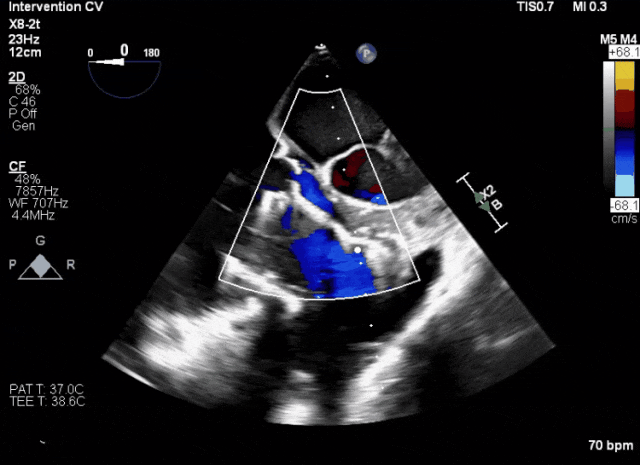

術前超聲顯示三尖瓣重度反流合并拴系